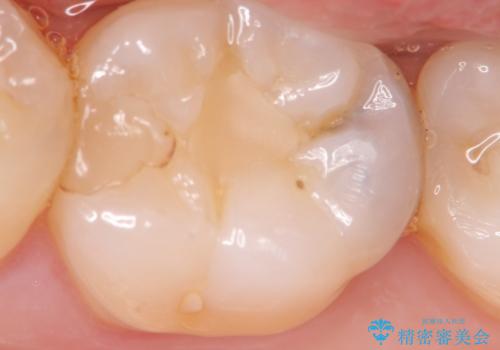

- 虫歯の検診を求めて来院されました。

X線検査により外から見てもわからない虫歯が認められたので、マイクロスコープ下で丁寧かつ徹底的に虫歯を除去しセラミックインレーによる修復を計画します。